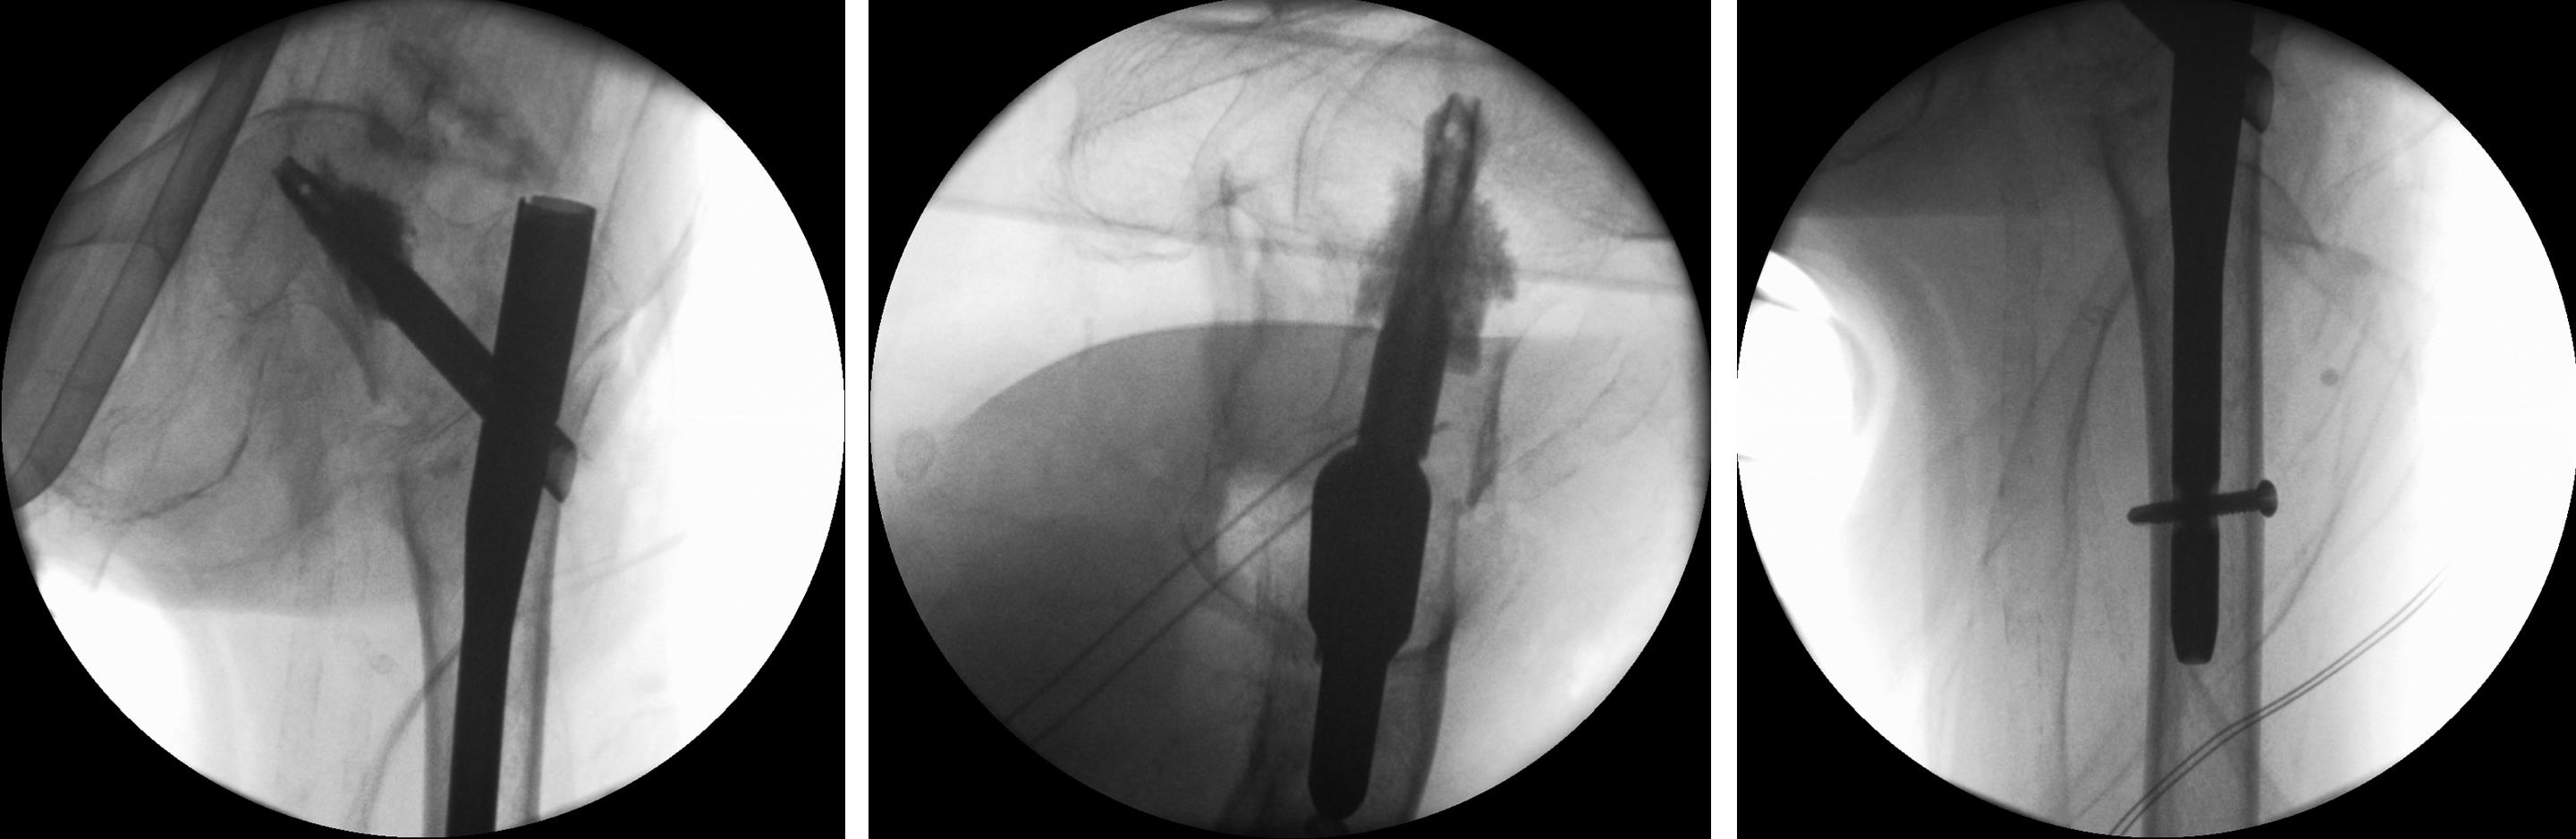

An 83-year-old female patient sustained a 31-A.2.2 fracture of the right proximal femur after a fall at home (Figs 1-2). Intraoperative and postoperative images are shown (Figs 3-5).

A 77-year-old man suffered a right femoral trochanteric fracture (Figs 5-8). This case can be diagnosed as AO31-A1. However, the CT shows the detachment of the lesser trochanter (AO31-A2). Precise information of dangerous fracture patterns in advance might simplify the imaging of intraoperative reduction maneuvers and the use of the implants.

In this case, the fracture lines are located in the area of the intended nail insertion point. The 3-D reconstruction images distinctly show that the hollow reamer prevented the fracture fragments from being pushed apart when introducing the hollow reamer close to the fracture line.